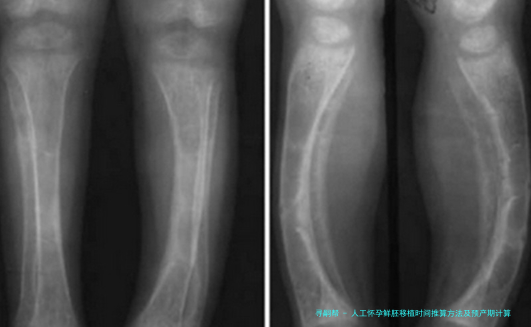

五、B超动态修正机制

孕早期通过量测胚芽长度(CRL)邃密调节孕周:

| 胚芽长度(mm) | 对应孕周 | 允许误差范围 |

|---|---|---|

| 3-5 | 6周+3天 | ±3天 |

| 16-18 | 8周+2天 | ±2天 |

胎心出现时间窗为孕5-6周,晚在自然中妊娠周期一周属正常范围。